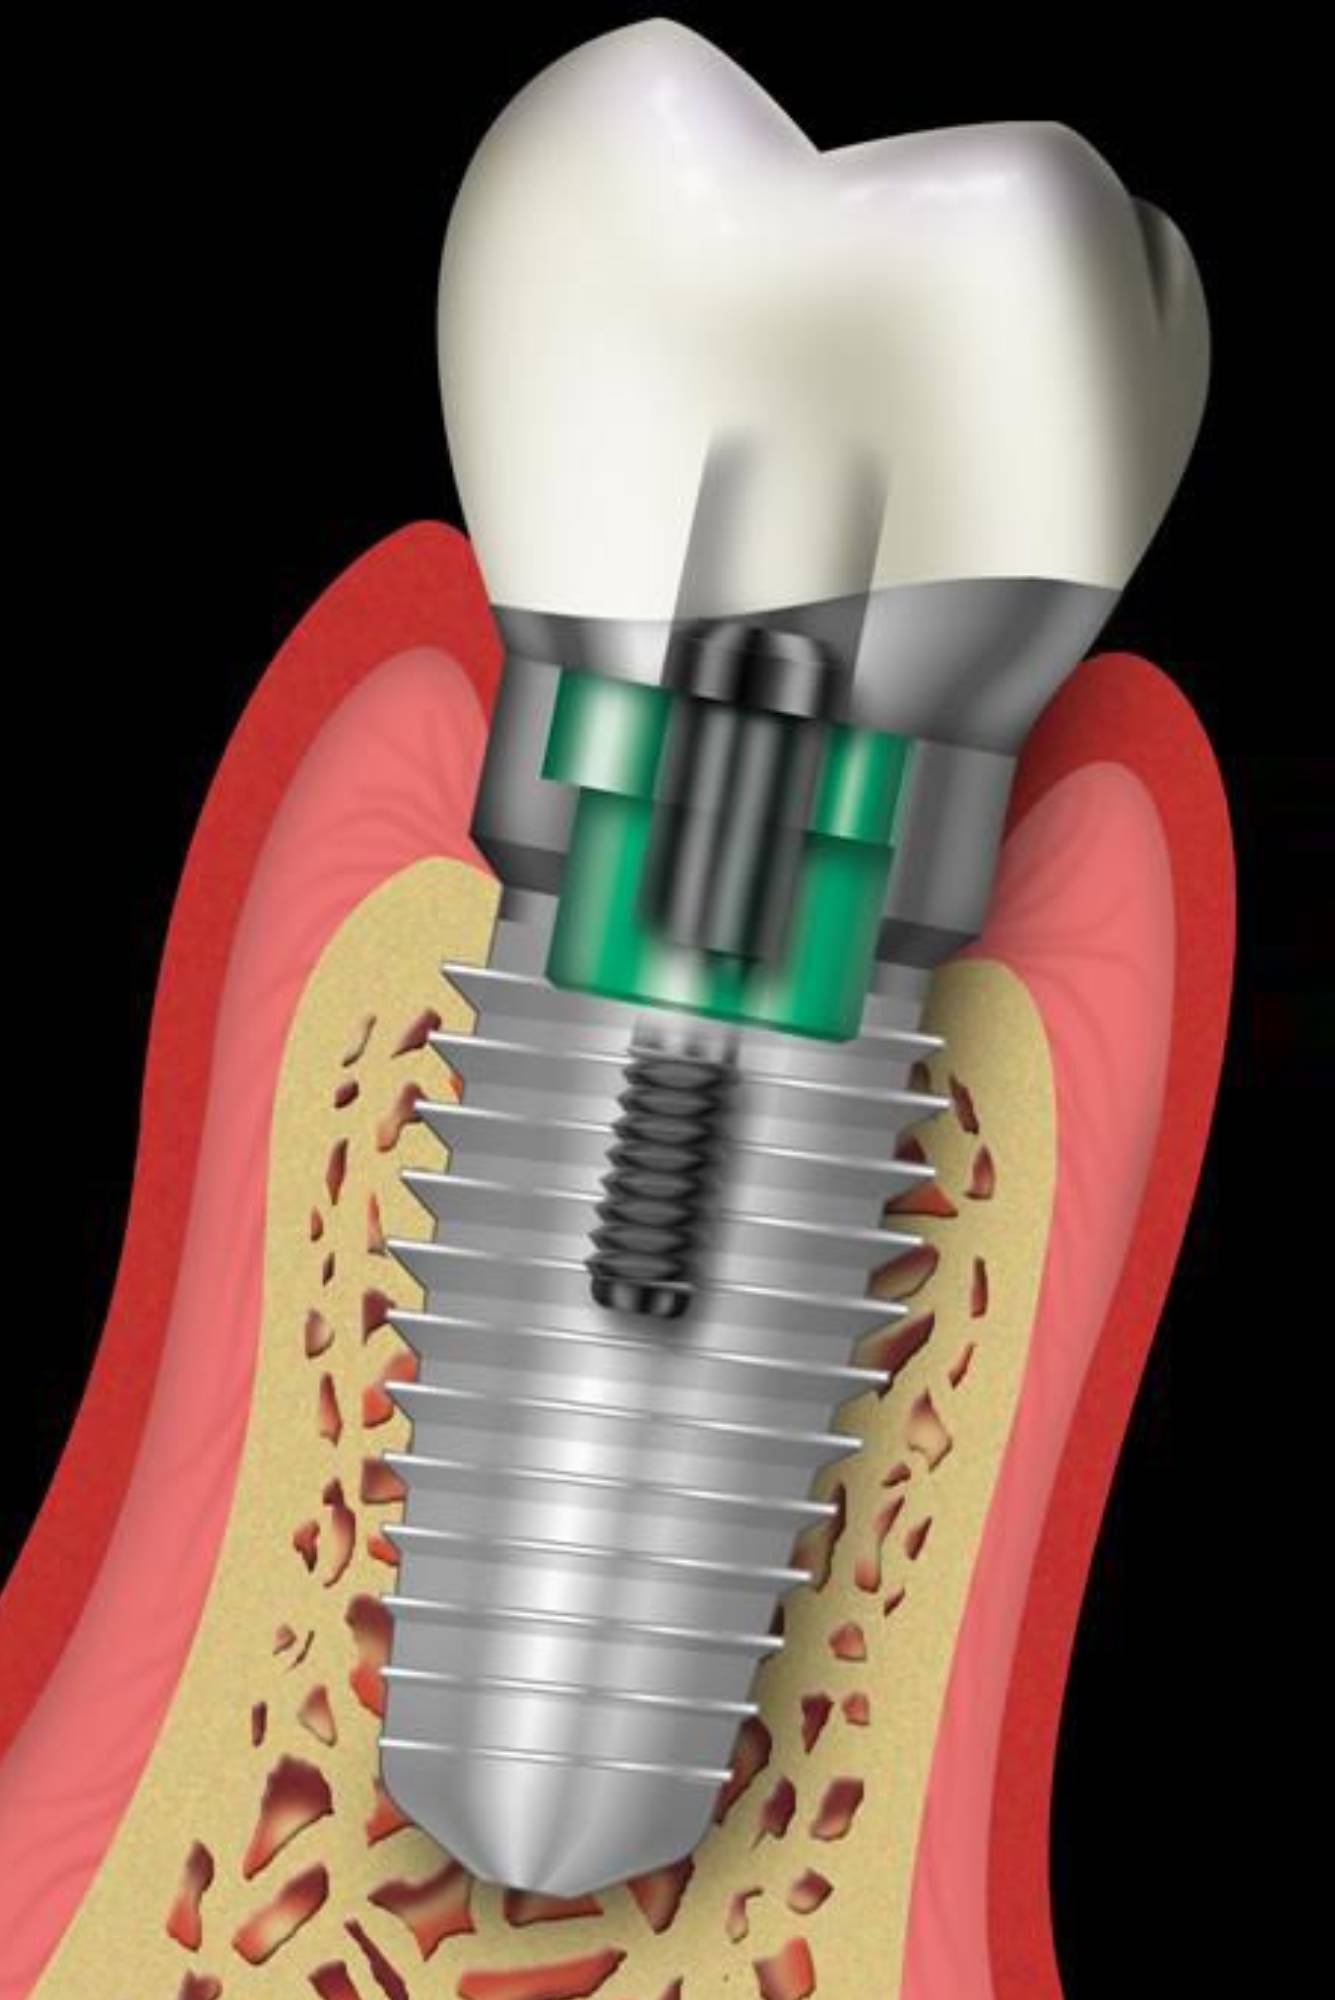

Рентген имплантов Alpha Bio: диагностика и качество